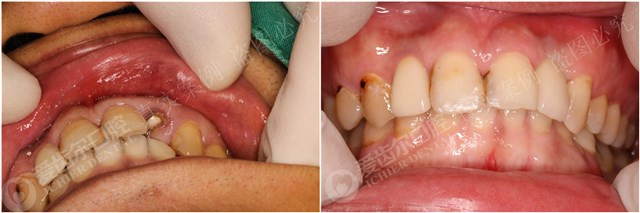

种植前,左上前牙因龋损折断,只剩龈下残根

种植中,种植体与牙组织密合

种植后,佩戴牙冠,无松动、无炎症等不良情况

种植前后对比图